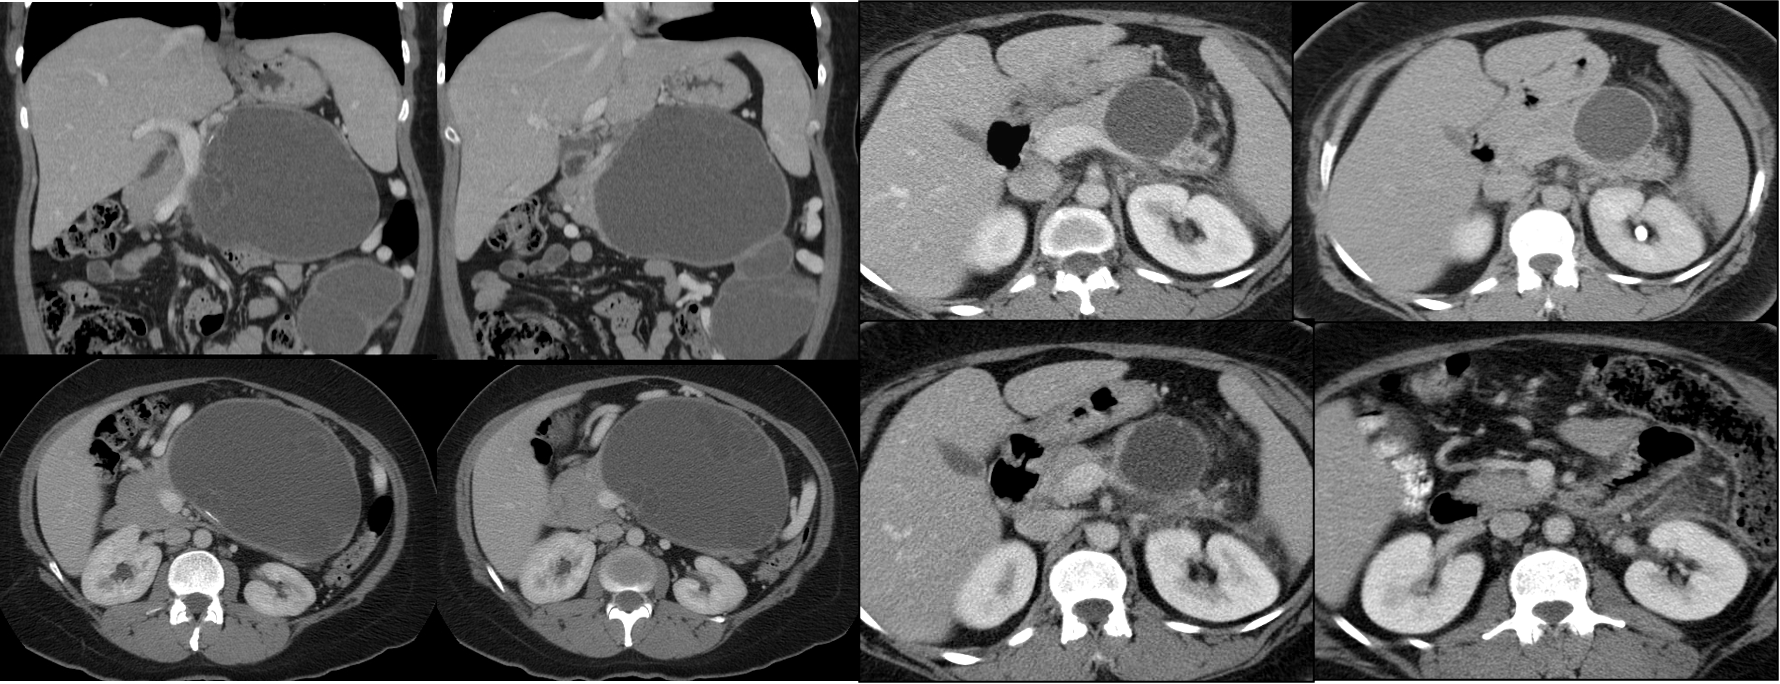

- Intraductal Papillary Mucinous Neoplasms. (IPMN) Y

- Older males.

- Arise in the head and uncinate process of the pancreas, and they are typically connected to the ductal system of the pancreas.

- IPMNs comprise lesions of the main pancreatic duct, side branches, or a combination.

- The prevalence of malignancy:

- lesions of the main-duct: 57–92%

- lesions of side-branch: 6–46%

- Mixed features of microcystic and macrocystic lesions.

- The main pancreatic duct is often dilated.

- Contain mucinous fluid which is sometimes extruding from the ampulla of Vater.